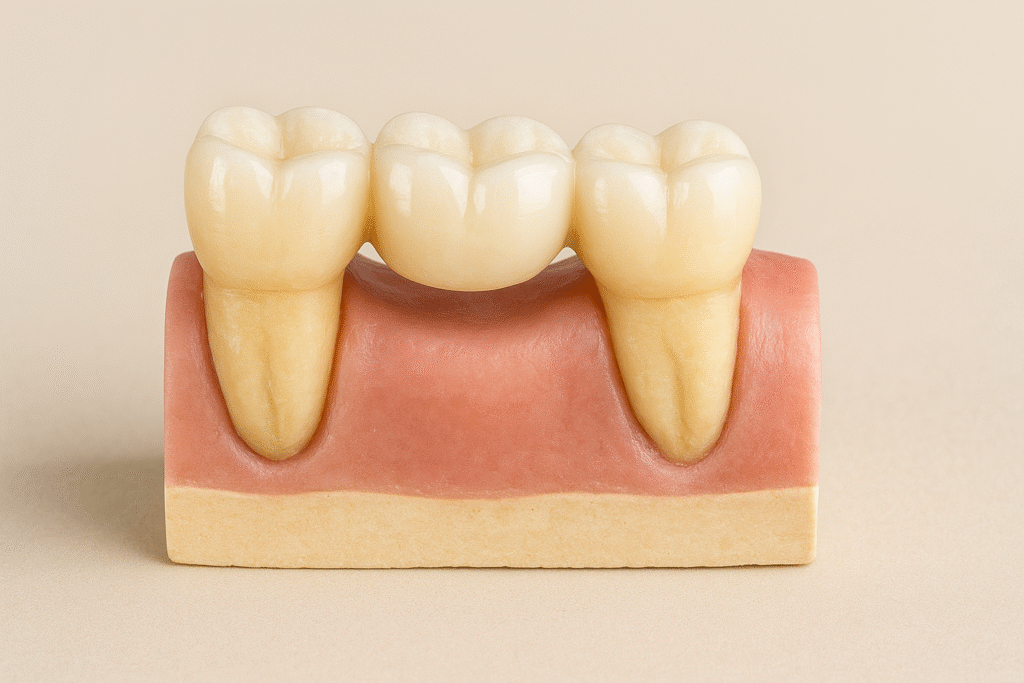

Unsere Kronen- und Brückenversorgungen werden vollständig digital geplant und konstruiert, um reproduzierbare Passungen und definierte Okklusionsverhältnisse sicherzustellen. Die Präparationsgrenzen werden sauber erfasst und in der CAD-Umgebung exakt übertragen, sodass die finale Restauration spannungsfrei sitzt und minimalen Nachbearbeitungsaufwand in der Praxis erfordert.

Je nach klinischer Situation setzen wir auf Zirkon, e.max oder metallkeramische Lösungen, um Belastbarkeit, Lichtdynamik und Randstabilität optimal zu kombinieren. Kontaktpunkte, Approximalkontakte und die funktionelle Morphologie werden bewusst ausgearbeitet, damit Eingliederung und Feineinstellung chairside effizient und vorhersehbar erfolgen können.

Durch unsere standardisierten CAD/CAM-Prozesse und abschließende manuelle Kontrolle entsteht eine Versorgung, die hohe klinische Langlebigkeit mit präziser Funktion verbindet.